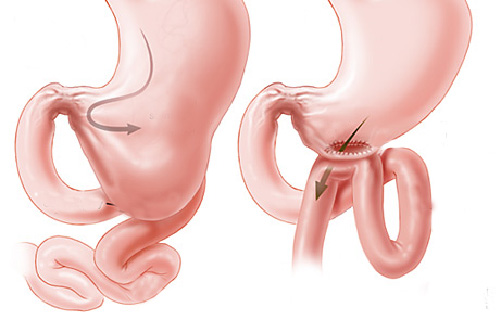

O que é um exame de CPRE (colangiopancreatografia retrógrada endoscópica)?

A CPRE é um procedimento que pode ser feito para examinar o fígado, vesícula biliar, vias biliares e o pâncreas. O fígado é um órgão que, entre outras coisas, produz um líquido chamado bile que auxilia a digestão. A vesícula biliar é um órgão pequeno, em forma de pêra, que armazena a bile até que seja necessária para a digestão. Os ductos biliares são canais que transportam a bile do fígado para a vesícula biliar e duodeno. Estes ductos são chamados algumas vezes de árvore ou via biliar. O pâncreas é um órgão que produz substâncias químicas que ajudam a digestão.

Com o paciente sedado, o aparelho é introduzido pela boca e passa através do esôfago e do estômago para o duodeno, local onde fica posicionada a papila duodenal.

Para o exame, o médico utiliza um tubo flexível e iluminado chamado duodenoscópio, que possui uma câmera na lateral do aparelho, diferente do endoscópico padrão que possui a câmera na frente do aparelho.

O médico verifica a abertura do tubo de drenagem de bile do fígado. Este tubo de drenagem é chamado de ducto biliar comum. Drena bile do fígado e suco pancreático para o duodeno para ajudar na digestão das gorduras. O orifício de saída do ducto biliar no parede do duodeno chama-se papila duodenal.

Durante o exame o médico passa de um pequeno cateter (tubo) dentro do ducto biliar comum e injeta um contraste que pode ser visto com um exame de raio-X. A via biliar e eventualmente o pâncreas podem então ser examinados para anormalidades.

A CPRE pode ser utilizada para o tratamento de pedras ou bloqueios nos canais biliares. Seu médico pode usar alguns acessórios para fazer um pequeno corte na parede do intestino, na abertura do duto biliar comum para alargar a abertura da papila duodenal. Este procedimento chama-se papilotomia endoscópica.

Após este procedimento, pode ser possível a retirada de cálculos da via biliar, permitindo assim o retorno normal da drenagem da bile do fígado para o duodeno.

Pode-se também realizar a passem de prótese através da abertura, para drenar a via biliar em caso de grande cálculos ou tumores que possam estar obstruindo a região.

Realizada em quase todos os exames de colangiopancreatogragia retrógrada endoscópica (CPRE), a papilotomia endoscópica é o procedimento de abertura do ducto biliar comum. Tem o objetivo de alargar a abertura da papila duodenal para a drenagem da bile com maior facilidade e para retirada de cálculos que podem estar obstruindo a saída da bile. Também é utilizada em cados de estreitamentos da via biliar, para que se possa utilizar os instrumento de dilatação como as próteses plásticas ou autoexpansíveis.

Durante a CPRE, após a cateterização da via biliar e infusão de contraste, realiza-se o RX, que pode mostar cálculos (pedras) que podem estar obstruindo a saída da bile e causando os sintomas no paciente.

Após este diagnóstico realiza-se o procedimento de papilotomia endoscópica, para poder alargar a saída do canal da bile. Com isto pode-se retirar as pedras da via biliar e permitir o retorno normal da drenagem da bile do fígado para o duodeno.

Geralmente a simples abertura da saída do canal da bile não é suficiente para que o cálculo saia. Nestes casos precisamos inserir instrumentos através do duodenoscópico como cestas ou balões para varrer de cima para baixo o canal da via biliar e assim conseguir extrair os cálculos.

Quando o calculo é muito grande, precisamos quebrá-lo para poder retirá-lo, este procedimento é chamado de litotripsia mecânica. Este é realizado através da captura do cálculo com uma cesta, sendo esta fechada até que o cálculo quebre.

Eventualmente se o cálculo não quebrar ou se for de tamanho muito grande, pode-se realizar a passem de prótese através da abertura, para drenar a via biliar e desobstruir a região.

Geralmente após realiza-se o exame novamente alguns dias depois para uma nova tentativa de retirada do cálculo por endoscopia. Se as tentativas por endoscopias falharem o paciente é submetido a cirurgia para a resolver definitivamente o problema.